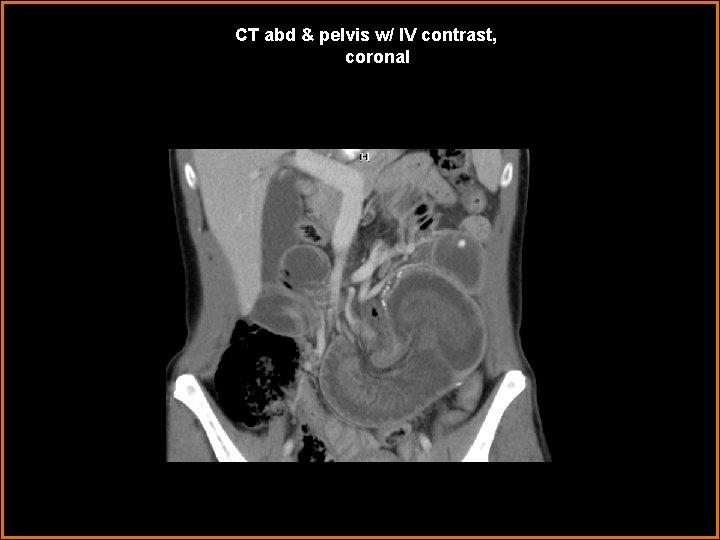

Case History 42 year-old female status-post gastric bypass operation within the last year presents with acute abdominal pain, nausea, and vomiting, for two days.

CT abd & pelvis w/ IV contrast, coronal

Findings and Differentials Findings: -- several centimeters of small bowel lumen-within-lumen appearance—“target / bull’s eye” appearance, in axial cross-section -- mesenteric fat and vessels enter at the most proximal end of this small intestinal “telescoping” -- dilated immediate distal or outer aspect of the telescoping bowel-in-bowel segment -- however, decompressed distal small bowel and decompressing colon -- surgical anastomotic small intestinal clips in mid abdomen nearby segment of jejunum enters a segment of distal jejunum, near a post-operative site Differentials: • Intussusception • Midgut volvulus

Diagnosis Jejuno-jejunal intussusception, with partial small bowel obstruction converting to completion